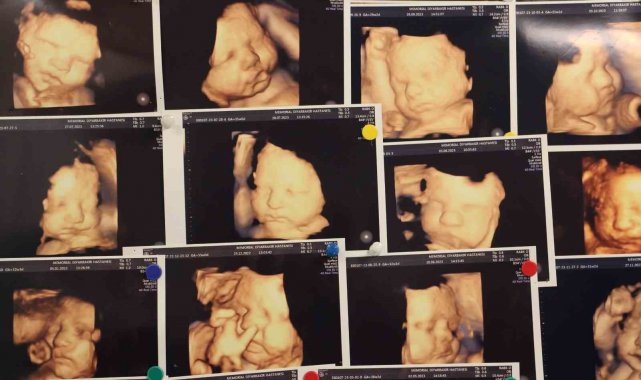

Memorial Hastanesi Kadın Hastalıkları ve Doğum Uzmanı Op. Dr. Gamze Akın Evsen, çocuk sahibi olmaya hazırlanan çiftlerin yaşadığı en büyük travmalardan biri olan gebelik kayıpları, çoğu anne adayının psikolojisinin bozulmasına ve çaresizlik hissine kapılmasına neden olduğunu belirterek, "Klinik olarak saptanan gebeliklerin yüzde 10-15'i düşükle sonuçlanmakla beraber bu durumun tekrar etmesi yani tekrarlayan gebelik kayıplarında oran Yüzde 3 ila 5'tir" dedi.

"Klinik olarak saptanan gebeliklerin yüzde 10-15'i düşükle sonuçlanmakla beraber bu durumun tekrar etmesi yani tekrarlayan gebelik kayıplarında oran Yüzde 3 ila 5'tir. Tekrarlayan gebelik kayıplarında en sık kromozomal sıkıntılar olmakla beraber, genetik anomaliler, hormonsal sıkıntılar, kan pıhtılaşması, rahmin yapısal bozuklukları, annede var olan diyabet ve guatr gibi sistemin hastalıklar, annede tekrarlayan enfeksiyonlar, bağışıklık sistemi sorunları ve çevresel faktörler görülebilmektedir."

Gebelik kayıplarının sebeplerinin değerlendirilmesi için çeşitli testlerin yapılması gerektiğini aktaran Dr. Evsen, "Özellikle tekrarlayan gebelik kayıplarının sebepleri değerlendirildiğinde öncelikle anne ve babanın kronik hastalıkları, tıbbi öyküleri, ailede mevcut genetik hastalıkları gibi durumların ayrıntılı bir şekilde sorgulanması gerekmektedir. Ayrıntılı bir fizik muayene sonrasında genetik sorunlar açısından genetik testi, pıhtılaşma bozukluğu açısından trombofili paneli incelenmesi, genel hastalıkların değerlendirilmesi için, akş, ogtt, hba1c, tsh, prl gibi testler istenebilmektedir. Yine bağışıklık sitemi değerlendirmesi için bazı testler istenmekle beraber rahmin yapısal sıkıntıları için hsg dediğimiz rahim filmi çekilmesi önerilmektedir. Tüm bunlar böyle kısaca özetlenebilse de bu süreç hasta için oldukça yıpratıcı kaygı verici olabilmektedir" dedi.